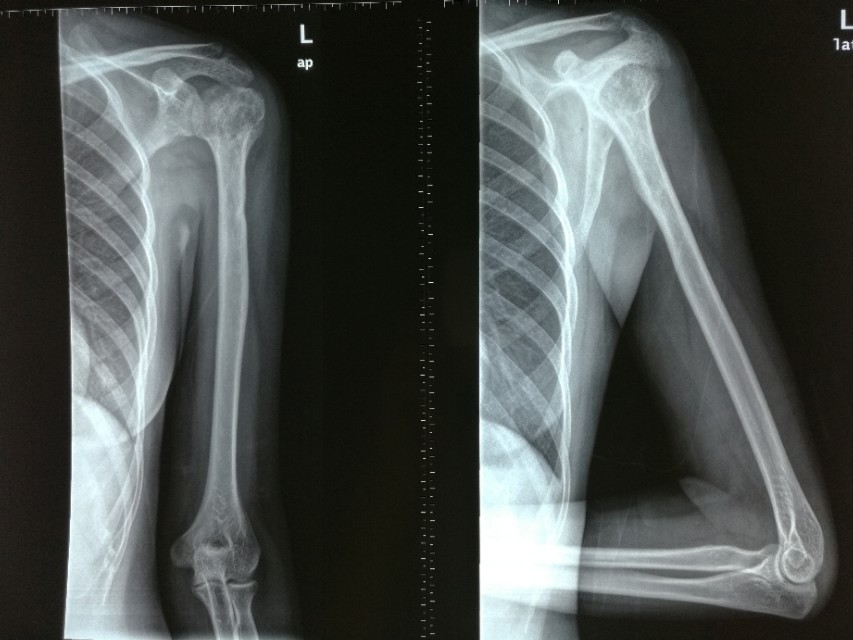

其他表现包括鼻腔、唾液腺组织和头颈部其他区域受累,溶骨性病变,肺结节,或者皮疹。X线等影像学可见占位性病变、溶骨性改变等!